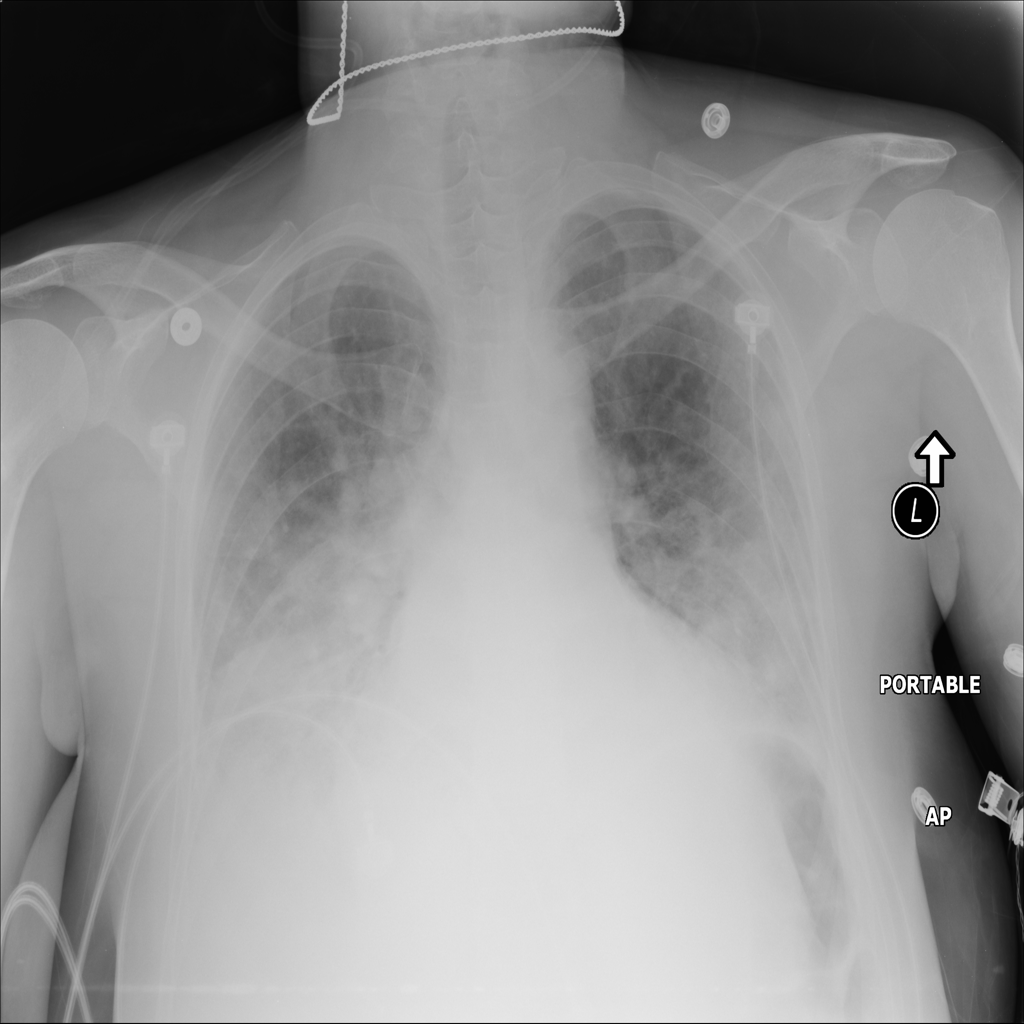

PAT-A1E2 · IMG-001Pneumonia

PAT-A1E2 · IMG-001

AP